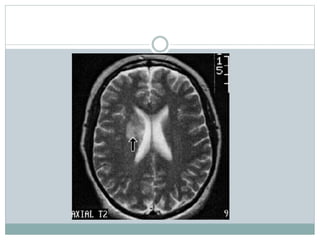

Neuroimagen

 Las neuroimagenes son de critica utilidad en los

pacientes con disfunción neurológica.

 La MRI es la única modalidad de imágenes

recomendada para la evaluación del Neuro LES.

Todas sus modalidades pueden ser usadas

 T-1 (atrofia) y T-2 (edema)

 FLAIR

 Contrastada con gadolinium

 DWI

MRI vs CT

 CT es útil para descartar un infarto o hemorragia

en un paciente con LES y deterioro neurológico

agudo.

 MRI es superior a CT para detectar edema,

infartos, y hemorragias.

 Sin embargo, ningún hallazgo de la MRI es

especifica para el NP-SLE.